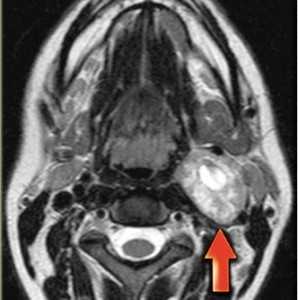

МРТ мягких тканей шеи. Т1-зависимая МРТ в аксиальной плоскости. Каротидная параганглиома справа.

МРТ мягких тканей шеи. Т2-зависимая МРТ в аксиальной плоскости. Невринома.

Невриномы также располагаются между крупными сосудами, отодвигая их. Опухоль округлая, с четким контуром, хорошо контрастируется и в отличие от параганглиомы не содержит сосудистых включений.